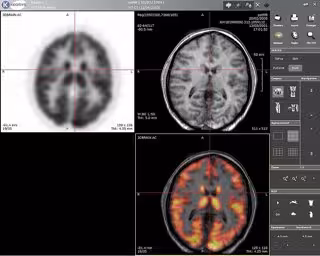

Los científicos, dirigidos por Stanislas Dehaene, utilizaron imágenes de resonancia magnética funcional (IRMf) para escanear el cerebro de 63 portugueses y brasileños que participaban en el estudio y que fueron divididos en tres grupos: adultos que no sabían leer, adultos que aprendieron a hacerlo de niños y adultos que aprendieron a leer de adultos. En contraste, la mayoría de experimentos de neuroimagen en adultos se suelen realizar en estudiantes con una educación elevada.

Los resultados mostraron que la lectura mejora el procesamiento de los estimulos visuales orientados horizontalmente en la corteza occipital y también conduce a la aparición de un área especializada para las palabras en la corteza temporal.

El área en la corteza temporal dedicada al procesamiento de caras se reduce, aunque los autores señalan que serán necesarias más investigaciones para determinar si esto hace que las capacidades de reconocimiento de caras se resiente por ello.